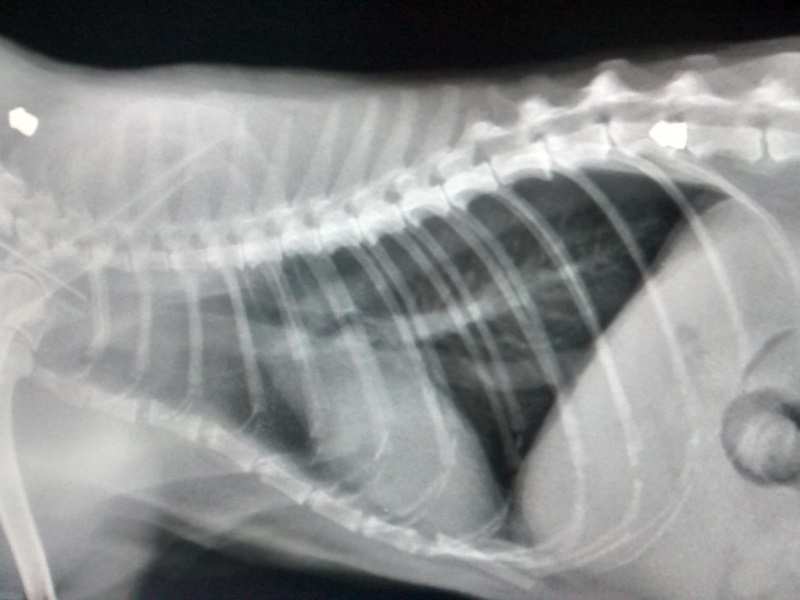

- Травма позвоночника. Одно из самых тяжелых и опасных состояний для кота — это повреждения позвоночного столба. Как известно, позвоночник играет важную роль во время передвижения животного, выполнения трюков, прыжков, бега. При заболевании данного отдела, питомец начинает вести себя странно. Сначала меняется походка, теряется активность. Со временем нарушения в позвонках приводят к развитию сопутствующих болезней. Состояние может привести к тяжелым последствиям и даже летальному исходу. Поэтому в первую очередь следует в домашних условиях провести прощупывание вдоль всего позвоночника, в том числе верхних отделов хвоста. Заметная реакция на надавливание может указать на место травмы. Для постановки точного диагноза необходимо сделать рентген всего столба. Если травма незначительная, то врач назначает комплекс витаминов, седативные препараты для спокойного поведения. В тяжелых ситуациях рекомендуется оперативное лечение;

Три месяца назад уезжали с мужем отдыхать на 2 недели, оставляли кота дома и просили знакомых приходить за ним ухаживать. Кот вообще очень боится всех посторонних людей, всегда как кто-то приходит прячется под диван и не выходит. Особенно почему-то боится детей, встает дыбом и шипит на них, такая реакция только на детей (у нас детей нет). Понимали, что сильно будет переживать разлуку, но с собой его взять никак не могли. Приходила ухаживать девушка, и как мы поняли по забытой у нас дома игрушке иногда с ребенком. По возвращению кот был не такой как обычно, более пугливый, вялый, не игривый, и ходил сгорбленно, изгибая спину при ходьбе как будто бы он только что проснулся, но он ходил так постоянно, как будто напряженно. Аппетит был обычный и туалет тоже. Еще он теперь не может нормально запрыгнуть на стул/диван, он теперь только вскарабкивается на них. Сразу всех недугов мы не заметили и думали что кот просто отвык от нас, привыкнет и будет передвигаться как обычно. Но нет, так и продолжалось. Мы подумали, что ребенок мог его за хвост пытаться вытащить из-по дивана и нарушил ему позвоночник, или ударил его чем-то пока мама ребенка убирала за котом. Повезли к ветеринару, сделали рентген, кости все в порядки, позвоночник цел, задние лапы тоже (при прощупывании позвоночник не болезнен). На рентгене увидели много застоялого кала по всему кишечнику, решили что из за этого он и ходит сгорбленно, поджимая живот. Врач сказал, что это у него скорее всего повышена кислотность желудка, поэтому вся влага из кала всасывается желудком и кал становится очень плотным и плохо выходит. Хотя у него всегда стул был одной и той же плотности, мы думали это нормально, оказалось нет. Подавали ему лекарства: алмагель, омез, метронидозол, ветом. Стул стал мягче, но кот оставался в том же сгорбленном состоянии. Затем кололи ему баралгин и синулокс, вроде кот стал чуть более активен. Затем взяли кровь на общий анализ и биохимию, все показало в норме, только показатель печени был немного отклонен от нормы. Подавали для печени ему гепатовед.